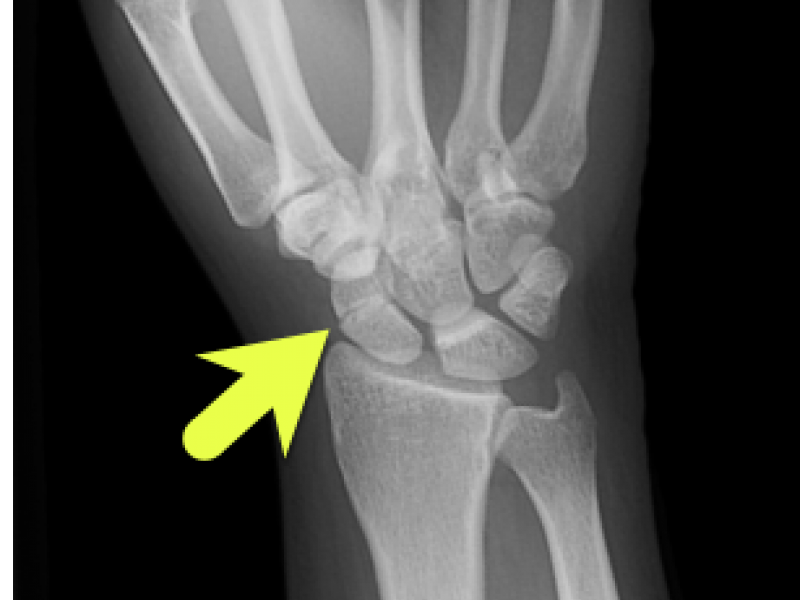

Answer: Non-displaced scaphoid waist fracture Scaphoid